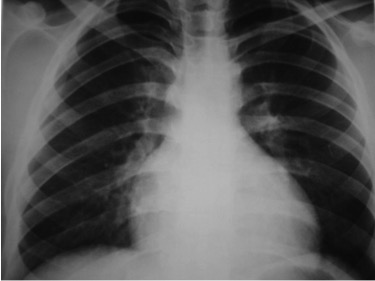

CASO: Paciente que tras esfuerzos de mucha intensidad siente palpitaciones.

Hallazgos:

- Borramiento de borde cardiaco derecho por Pectus Excavatum.

- Parénquimas pulmonares sin alteraciones radiológicas significativas.

El diagnóstico es clínico. Con la imagen evaluamos mejor la deformidad, útil en caso de ser necesaria la cirugía.

En la Rx de tórax se observa el borramiento del borde cardiaco derecho y en la placa lateral, la depresión interna del esternón, característicamente del cuerpo esternal y de la apófisis xifoides. En casos más acentuados, el corazón, los pulmones, el esófago y el diafragma pueden estar comprimidos, con desplazamiento del corazón hacia la izquierda y prominencia del tronco de la arteria pulmonar en la proyección PA; hallazgos mas evidentes gracias al TC y las reconstrucciones.